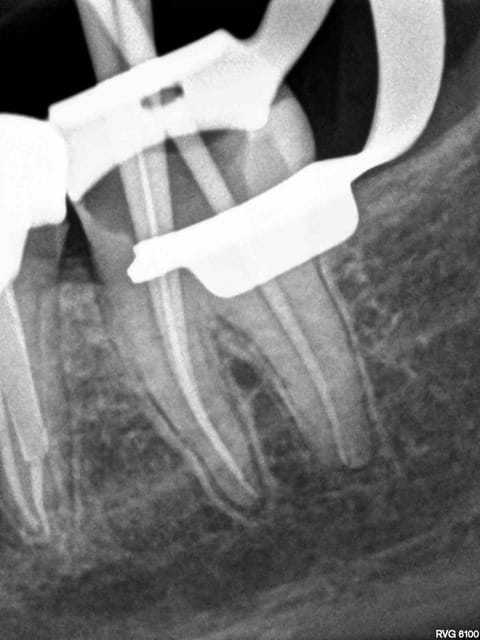

J'y travaille pour trouver un moyen simple et efficace pour poser la digue dans toutes les situations comme celle ci dessous. Tiens c'est tout frais, endo sc33 en 1 temps, 1H 15 et encore je n'ai pas d'assistante au fauteuil.

Technique "Monocône"....C'est un peu "has been" je trouve.... ;-)

Pulpite indication endo. perte de substance: Indication onlay , mais pas dans le panier de soins donc sc 33, couronne coulée : patiente CMU.

Dis donc chicot t'es peut être le roi de l'endo mais au niveau économie tissulaire , ouverture de chambre , tu utilises un black et decker comme contre angle ?... t'y vas pas de main morte ... t'aurais peut être pu éviter le tenon alors , et qui sait la couronne .... et puis un genre screw post titane ? avec un matériau plastique perso je trouve pas ça terrible ... mais je ne suis qu'une petite dentiste qui utilise encore l'amalgame ... houuuu la méchante .....bon et puis la (ou le ) mitrailler comme ça pendant le soin juste pour nous montrer , faut pas tu sais , tu perds un temps fou ... après le temps de poster tout ça ..... t'imagines le temps perdu pour la rentabilité du cabinet ....

Surtout mono-cone sans ciment. mais c'est vrai que quand on ne fait pas d'essayage de cones on ne risque pas de voir pas la différence.-))))

Mais je ne me cache pas que je les scelle de temps en temps. Mais manque de bol pas là. Thermo compactés au mac spaden. Tu vois peut être la différence non ?